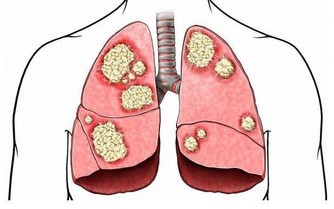

糖尿病屬於一種代謝性疾病,目前對於它並沒有治癒的方法,只能依靠藥物和飲食來控制,因此對於糖尿病要及早防治。糖尿病在早期會出現一些症狀,大家可以了解一下,以便及時發現和控制,且更好的防止並發症的發生。下面來看看糖尿病的六大標誌表現。

6、傷口難癒合

糖尿病的發生會阻礙血液流通,從而可導致傷口癒合時間延遲,甚至還可損傷神經組織。因為皮膚的傷口癒合需要充分的血液流通,否則會降低治愈能力,如發現有傷口血流不止等異常現象的,建議要及時到醫院接受診斷。